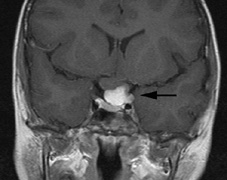

syndrome in 1926. The term von Hippel-Lindau syndrome (VHL) was

first used in 1936.166 The first major clinical criteria for the syndrome were proposed in 1964.167 The main manifestations of von Hippel-Linau syndrome are: histologically similar hemangiomas of the retina and CNS, renal cysts, renal cell carcinomas, pancreatic cysts, pheochromocytomas, and endolymphatic sac tumors.13 EPIDEMIOLOGY The prevalence of VHL syndrome is about 1 in 35,000 to 40,000.168 It is autosomal dominant with greater than 95% penetrance by age 60 years.169 Its expression, even within the same family, may be quite variable, especially for renal disease and pheochromocytoma.170,171 SYSTEMIC FEATURES Cutaneous Findings Cutaneous findings are not part of the diagnostic criteria for VHL syndrome. Neurologic Findings CNS hemangiomas are the most common tumor of VHL, affecting 60% to 80%, with a predilection for the cerebellum and spinal chord. An enlarging cystic component is a frequent finding in symptomatic tumors. Patients typically present in their early 30s; headaches or neck pain in affected individuals should not be ignored.172,173 On microscopy, CNS hemangiomas resemble retinal capillary hemangiomas. Their malignant potential is low.174 The treatment is surgical (Fig. 17, A and B).13 Endolymphatic sac cystadenomas are a sensitive marker of VHL. Patients may present with hearing loss, tinnitus, disequilibrium or facial nerve palsy.175,176 Visceral Findings KIDNEY. Renal cysts are often asymptomatic and do not require treatment. However, complex cysts may carry a risk for malignant transformation. Renal carcinoma affects about a third of patients. Patients typically present in their late 30s. These tumors may be completely asymptomatic, underscoring the necessity for ultrasound screening.13,177 ADRENALS. Pheochromocytomas are benign neural crest tumors of the adrenal medulla (chromaffin cell derived) and probably affect 10% to 20% of patients. Mean age at diagnosis is at about 30 years of age. Pheochromocytomas may be multiple and bilateral. They are catecholamine-secreting tumors that classically produce severe hypertension and anxiety attacks, but they may also be asymptomaic.178 The National Cancer Institute classification of VHL syndrome is in part based on the absence (type I) or presence (type II) of pheochromocytoma (Table 5).171